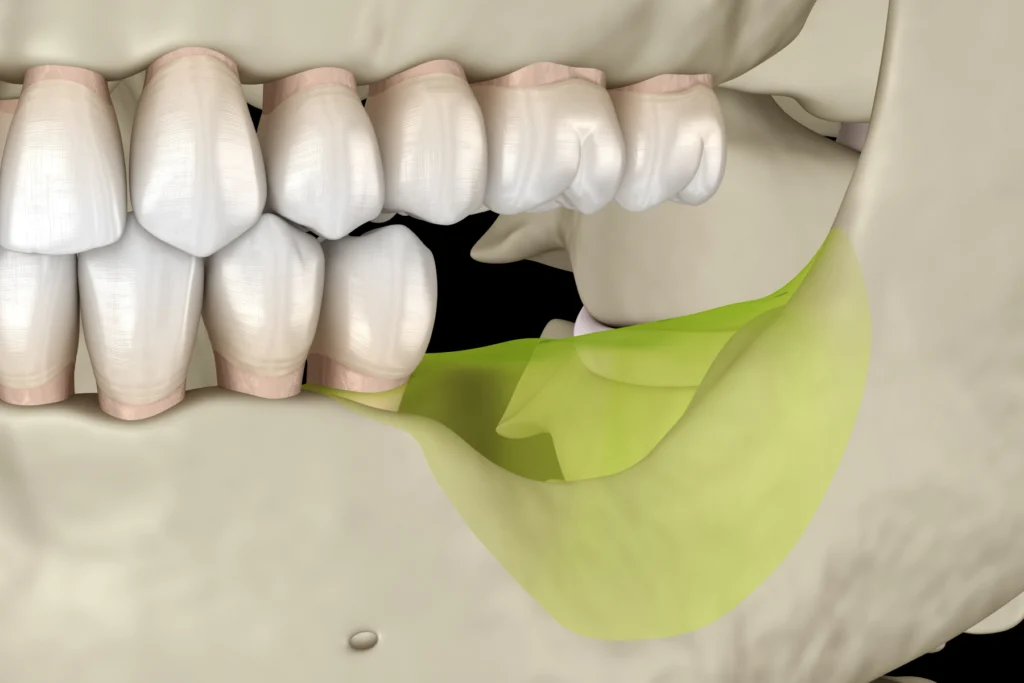

Implants dentaires

Les implants dentaires permettent de remplacer une ou plusieurs dents manquantes de manière durable.